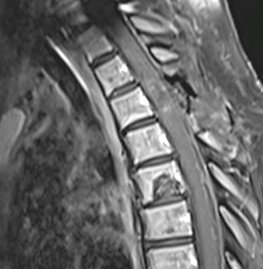

Intervenția chirurgicală a avut loc în bune condiții, reușind să extirpăm în cvasitotalitate țesutul tumoral fără a agrava pacienta din punct de vedere neurologic. RMN-ul de control efectuat a doua zi a confirmat absența rezecția completă precum și absența complicațiilor postoperatorii. Din punct de vedere neurologic, evoluția a fost favorabilă, cu ameliorarea treptată a deficitului motor sub kinetoterapie, pacienta putând fi mobilizată începând cu a doua zi postoperator, ulterior putându-și continua tratamentul oncologic: radioterapie spinală, apoi chimioterapie sistemică și interatecală.